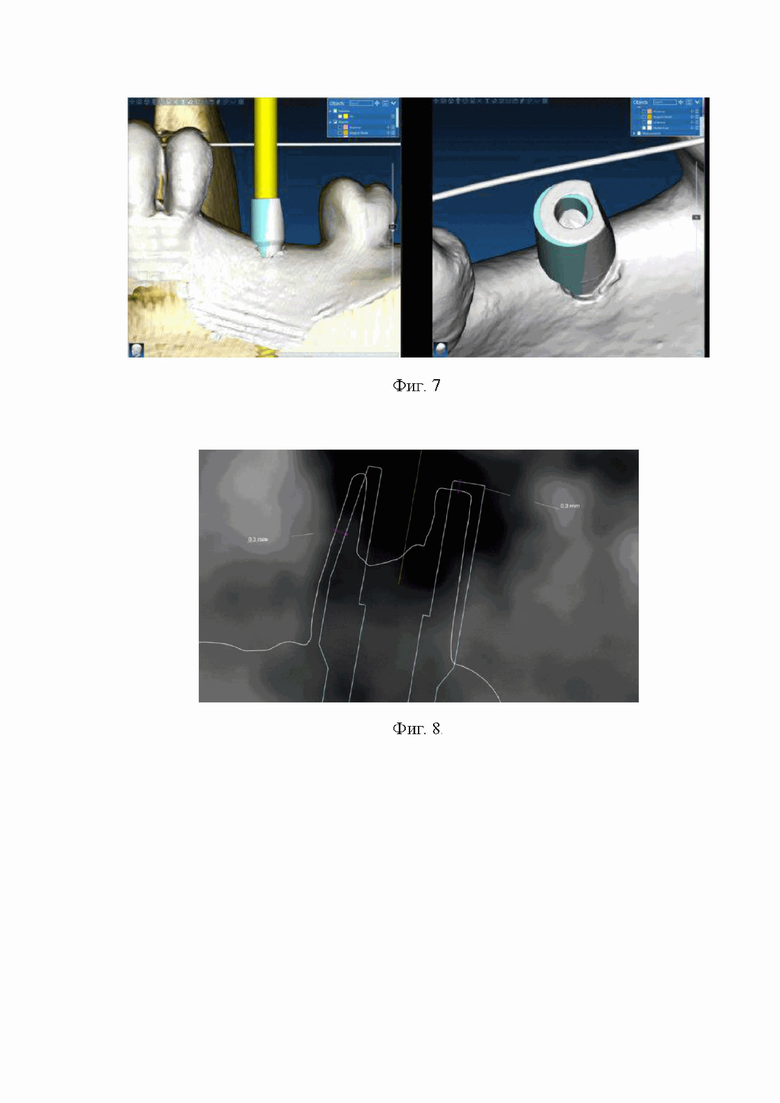

В программе для планирования дентальной имплантации RealGuide по общим статическим меткам, роль которых исполняли зубы, сопоставляли виртуальные модели имплантата с фиксированным скан-маркером полученные на этапе планирования, и оптические слепки системы - имплантат-скан-маркер, полученными после установки имплантата в фантомную модель (фиг. 7).

Расстояние между параллельными прямыми проведенными по касательной верхней части виртуальных моделей двух скан-маркеров соответствующий отклонению по глубине фактически установленного имплантата от планируемого, составил 0,3 мм (фиг. 8).

Фиг. 7. Сопоставления виртуальных моделей скан-маркеров, полученных при планировании планирования имплантации и после её проведения.

Фиг. 8. Измерения погрешности установки дентального имплантата по вертикали и горизонтали в пришеечной его части.